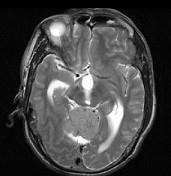

问题 男,61岁,头晕头痛伴行走不稳1月余,请根据所提供图像,选择最可能的诊断()

选项 A.胶质瘤 B.髓母细胞瘤 C.(天幕切迹缘)脑膜瘤 D.转移瘤 E.淋巴瘤

答案 C